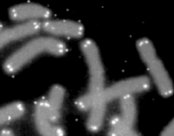

Telomeres (white) cap the ends of human chromosomes (gray). Image credit: U.S. Department of Energy Human Genome Program.

Right: Telomeres (white) cap the ends of human chromosomes (gray). Image credit: U.S. Department of Energy Human Genome Program. [More (http://gslc.genetics.utah.edu/features/telomeres/)]